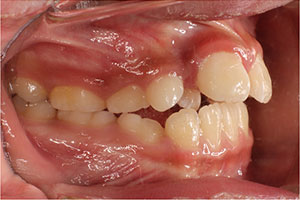

こちらの初診(男性)の患者さんは、開咬合 / 叢生歯列の症状がありました。

1期治療 8歳9ヶ月 2期治療 12歳4ヶ月から治療を開始し、1期治療 7ヶ月 2期治療 2年5ヶ月の間、スタンダードエッジワイズ法(与五沢エッジワイズシステム)を用い矯正治療を行いました。

| 症例分類 | 開咬合 / 叢生歯列 / 偏位咬合 | |||||||||||||||||||||||||||||||||||||||||||||||||||||||||||

| 動的治療期間 | 1期治療 7ヶ月 2期治療 2年5ヶ月 | |||||||||||||||||||||||||||||||||||||||||||||||||||||||||||

| 8歳9ヶ月 | 9歳8ヶ月 | |